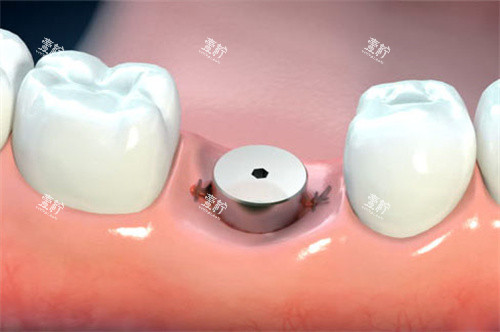

单颗种植牙愈合基台

适用场景:前牙区缺失、急需修养美观的患者。

比如有位教师缺了门牙,用即刻种植技术,当天就戴上了临时牙冠,第二天正常上课。

数据支撑:临床显示,即刻种植的成功几率达95%,与传统种植牙(96%-98%)接近,但修养时间缩短80%。